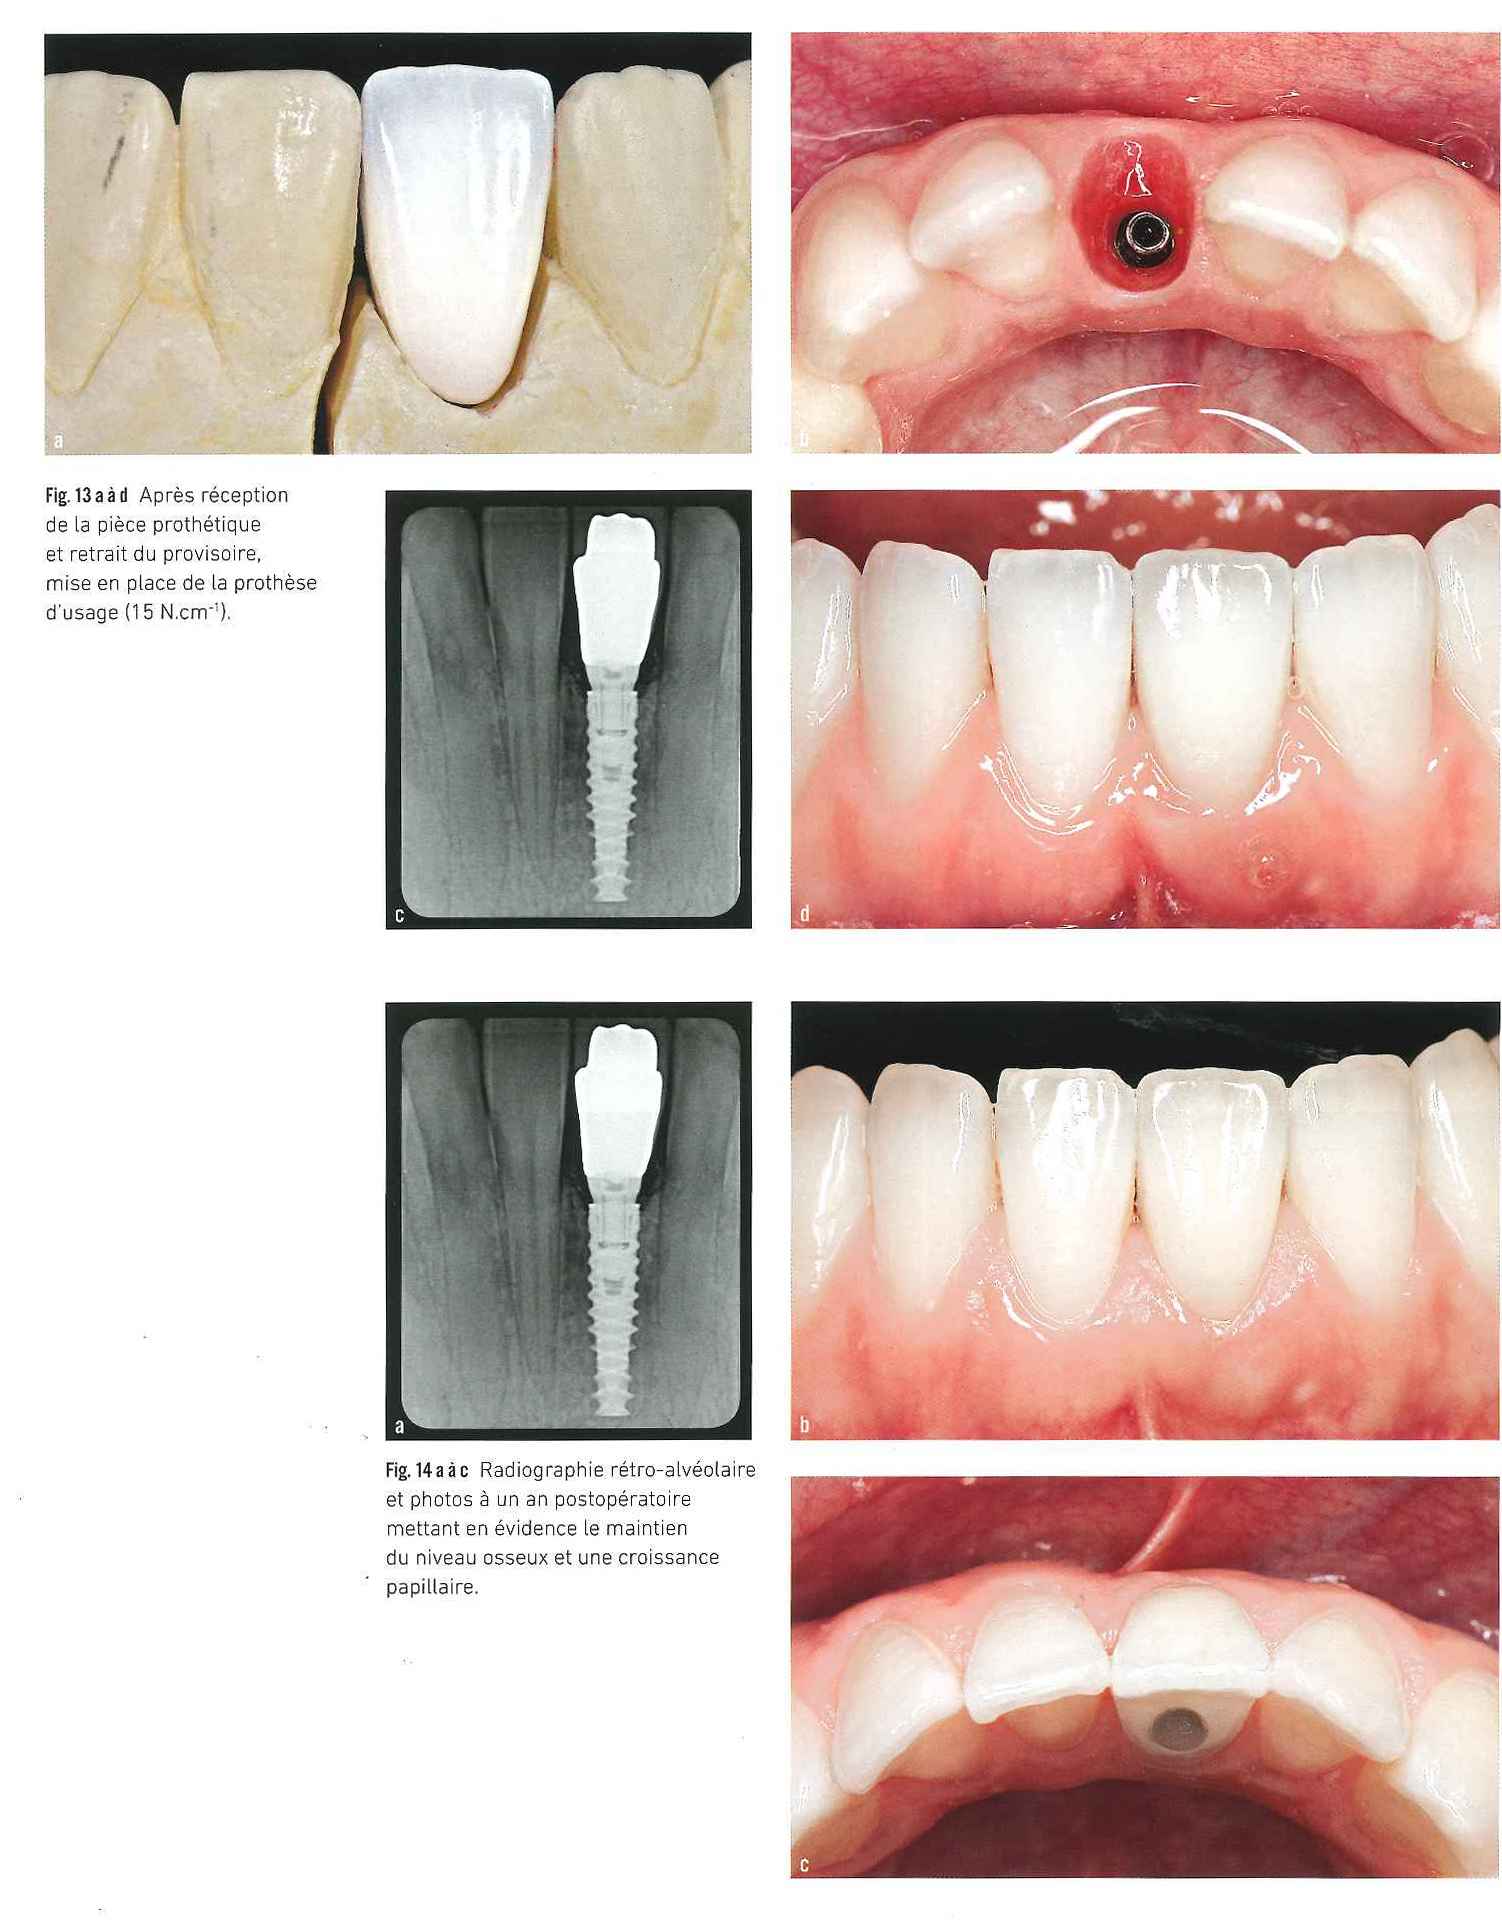

Réhabilitation esthétique et espace implantaire réduit